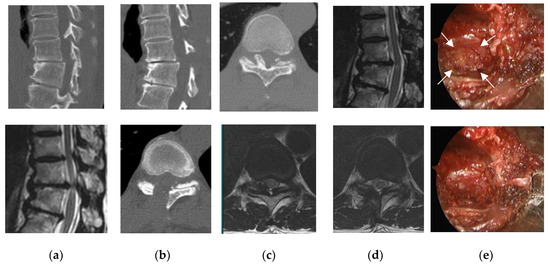

2.2. Surgical Technique